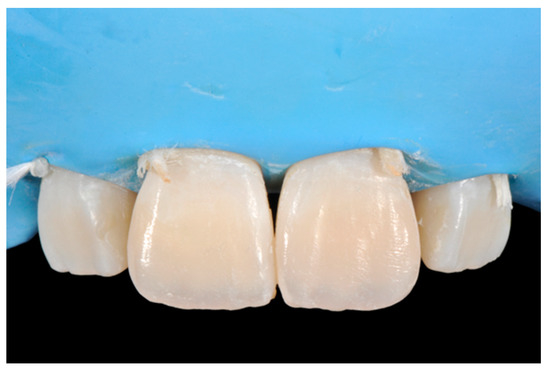

Finishing and polishing procedures were performed with a diamond bur (WL 268 014 Horico, Berlin, Germany), silicone points (Identoflex, Kerr, Bioggio, Switzerland) brushes (Jiffy Goat Air Brushes, Ultradent Products, South Jordan, UT, USA), and diamond pastes (Diamond Polish Mint, Ultradent Products, South Jordan, UT, USA) (Figure 13 and Figure 14). Satisfactory clinical and radiographic outcome was considered satisfactory at 3-months, 1-year, and 5-years post-operative (Figure 15, Figure 16, Figure 17, Figure 18 and Figure 19).

Figure 14.

After vertical and horizontal anatomy definition and final polishing. Reprinted from Restauri diretti nei settori anteriori, G. Paolone, S. Scolavino, © 2021, with permission from Quintessence Publishing Italy.